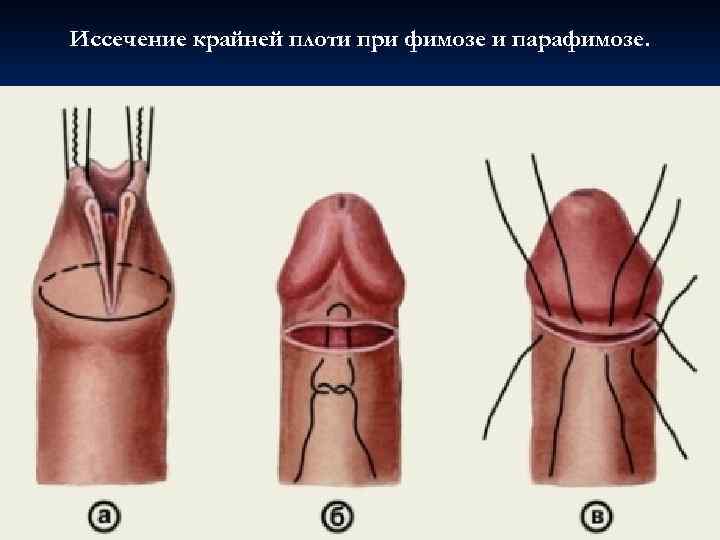

Фимоз – сужение наружного отверстия крайней плоти полового члена. Парафимоз — ущемление головки полового члена патологически сжатой кожей крайней плоти. В результате кольцеобразного ущемления головки члена крайней плотью нарушается кровоснабжение, возникает значительный отек головки. Баланит — воспаление кожи головки полового члена. Постит — воспаление внутреннего листка крайней плоти. У необрезанных мальчиков, юношей и мужчин баланит и постит всегда сопровождают друга, и в этом случае говорят о баланопостите.

Фимоз – сужение наружного отверстия крайней плоти полового члена. Парафимоз — ущемление головки полового члена патологически сжатой кожей крайней плоти. В результате кольцеобразного ущемления головки члена крайней плотью нарушается кровоснабжение, возникает значительный отек головки. Баланит — воспаление кожи головки полового члена. Постит — воспаление внутреннего листка крайней плоти. У необрезанных мальчиков, юношей и мужчин баланит и постит всегда сопровождают друга, и в этом случае говорят о баланопостите.

Иссечение крайней плоти при фимозе и парафимозе.

Иссечение крайней плоти при фимозе и парафимозе.